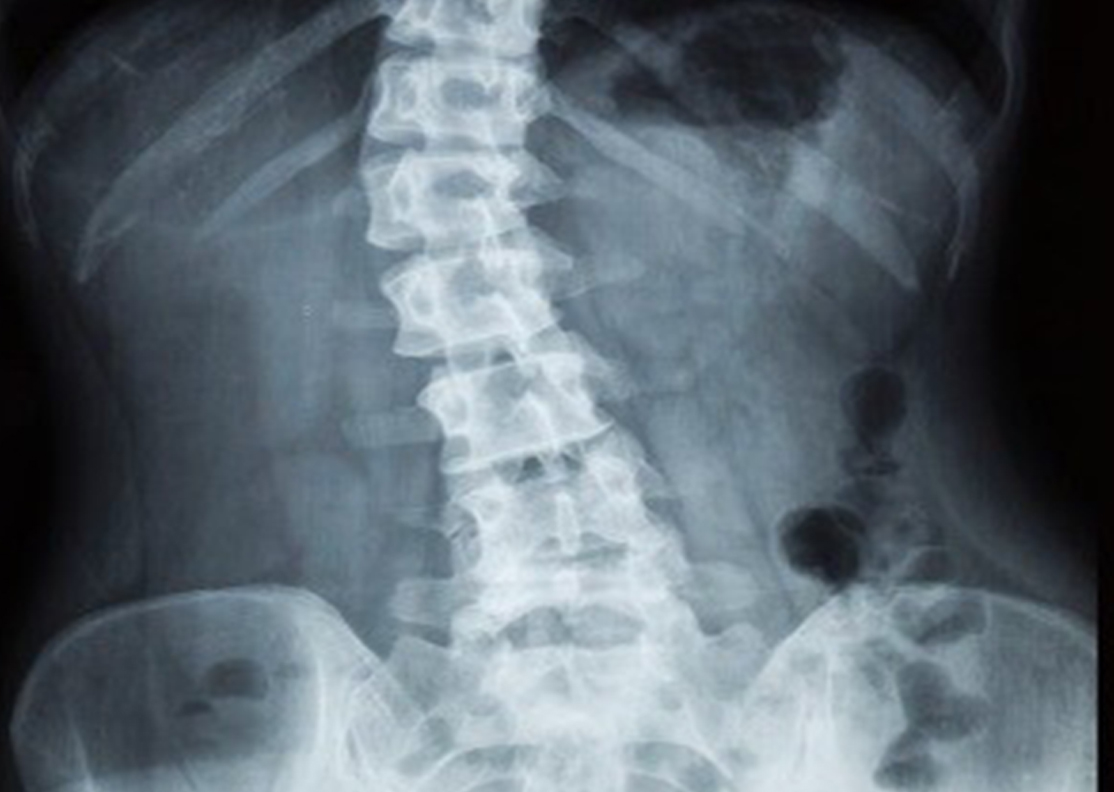

Escoliosis

La escoliosis es una desviación lateral de la columna vertebral que se produce a nivel de la zona lumbar y/o dorsal. La causa generalmente es desconocida (idiopática) aunque puede deberse a factores congénitos o neuromusculares. Se caracteriza principalmente por generar dolor en ciertas zonas de la espalda debido a desbalances musculares y posturas inadecuadas.